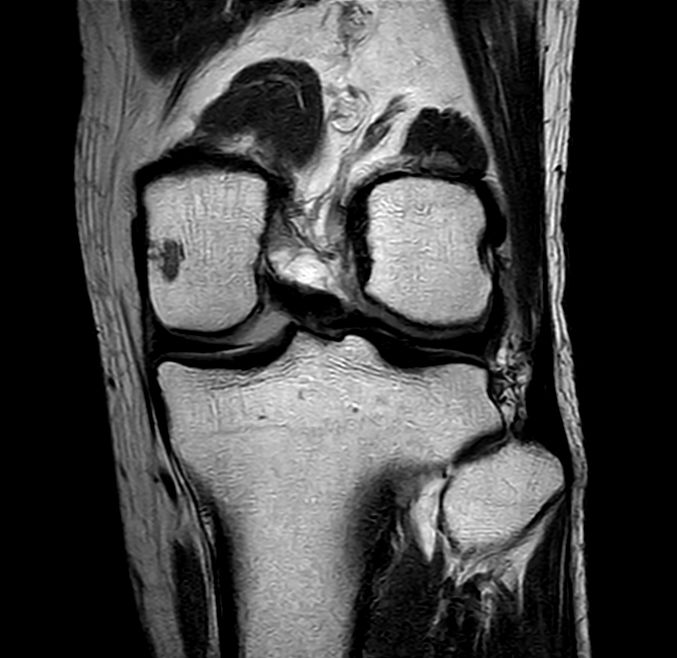

Coronal PDw TSE